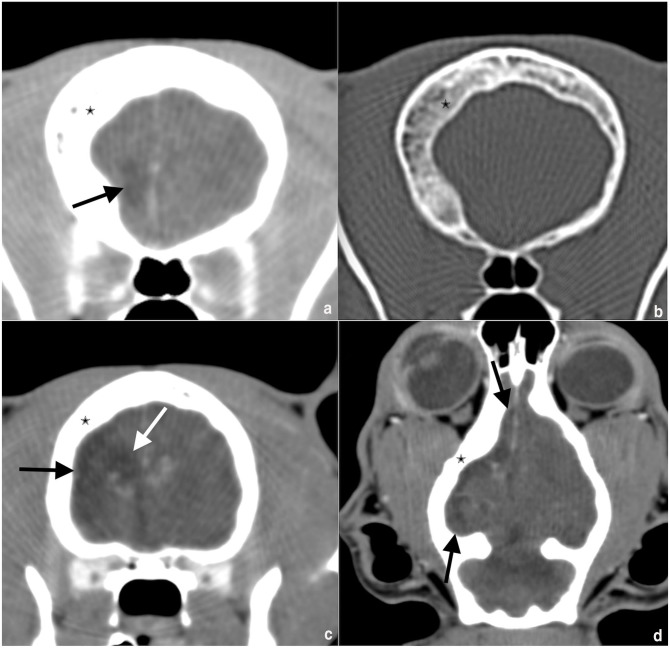

病例摘要:一只 4 岁大的猫咪因急性发作侧向神经性中枢神经系统(CNS)症状和癫痫发作而就诊。血液和血清生化指标均在正常范围内。影像诊断显示右脑 CT 和 MRI 严重异常,类似于人类医学中的戴克-达维多夫-马森综合征(DDMS)。该综合征包括脑半球萎缩、代偿性颅骨骨质增生和脑室肥大。这种变化以前仅在一例年龄相仿的猫科动物身上出现过一次。在人类,DDMS 被描述为胚胎和围产期发育障碍或幼年期获得性损伤:本病例报告表明,在一些罕见的成年猫病例中,如果没有进一步的影像学诊断,先天性疾病可能会被忽视,而这些病例的首次临床症状出现得较晚。

Case summary: A 4-year-old cat was presented with acute onset of lateralised neurological central nervous system (CNS) signs and seizures. Haematological and serum biochemical parameters were within normal limits. Imaging diagnostics revealed severe CT and MRI abnormalities of the right brain, similar to Dyke-Davidoff-Masson syndrome (DDMS) in human medicine. This syndrome includes cerebral hemiatrophy with compensatory calvarial hyperostosis and ventriculomegaly. Such changes have previously been reported only once in a single feline case of approximately the same age. In humans, DDMS is described as an embryonic and perinatal developmental disturbance or an acquired injury in early childhood.